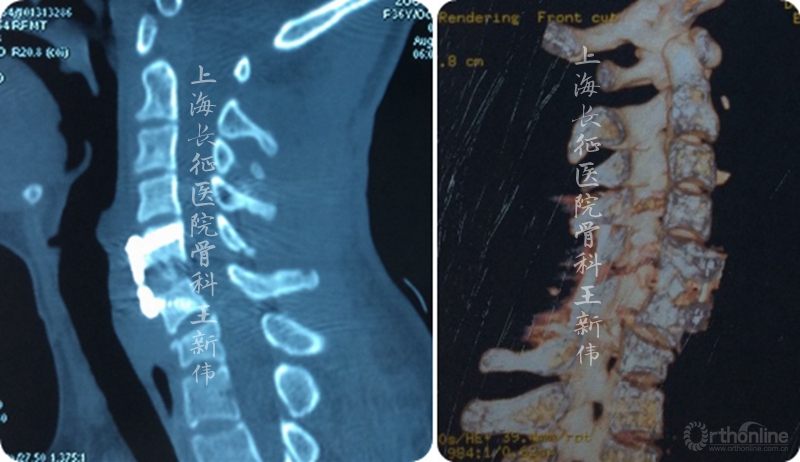

第一次术后颈椎CT三维重建,可见C6/7双侧仍存在关节绞锁

第二次术前颈椎MRI平扫,可见C6/7存在成角畸形,脊髓受压

考虑到患者C7存在骨折楔形变,C6/7术后仍存在关节突绞锁,椎间成角畸形,脊髓受压,再次手术解除脊髓成角畸形,解除后方小关节绞锁,改善SVA等等均是手术亟待解决的目标。

术中翻身行前路手术,鉴于C5-6椎间融合充分,仅行钢板去除,C6/7椎间减压cage植骨钢板内固定术,术中拍摄X线片即见颈胸成角畸形改善,SVA明显改善,关闭手术切口,术毕。